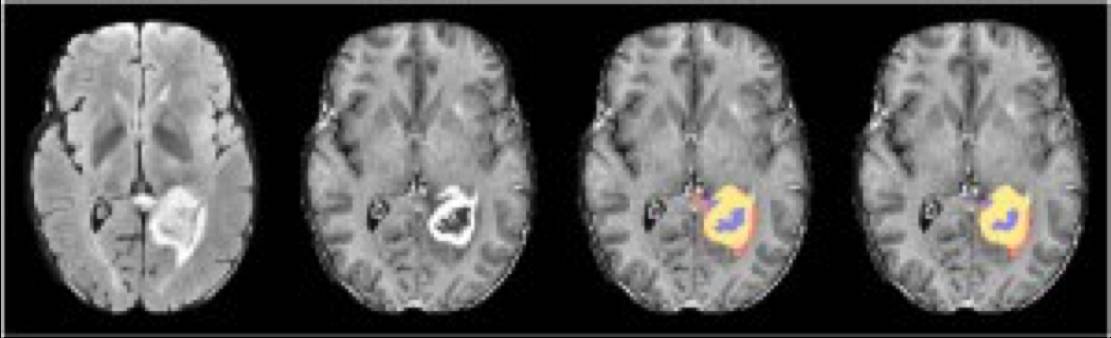

脑出血区域自动标记